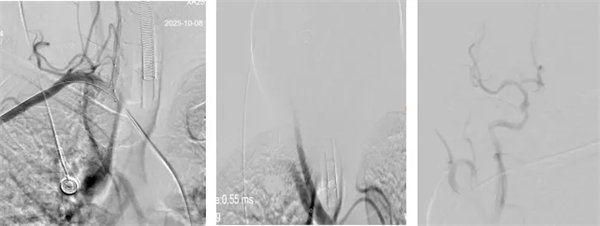

術(shù)中,介入團(tuán)隊(duì)精準(zhǔn)定位血管閉塞部位,通過(guò)微導(dǎo)絲“探路”聯(lián)合球囊擴(kuò)張技術(shù)開(kāi)通右側(cè)椎動(dòng)脈開(kāi)口,造影椎開(kāi)口殘余狹窄60%。基底動(dòng)脈血栓形成,基底動(dòng)脈管腔狹窄55%,基底動(dòng)脈尖堵塞,右側(cè)大腦后動(dòng)脈及小腦上動(dòng)脈未見(jiàn)顯影,左側(cè)大腦后動(dòng)脈P3以遠(yuǎn)閉塞。

席聰準(zhǔn)確鎖定患者基底動(dòng)脈處血栓,采用抽吸取栓技術(shù)快速開(kāi)通血管,成功取出堵塞部位2cm的血栓。再次造影示:右側(cè)大腦后及雙側(cè)小腦上動(dòng)脈再通,右側(cè)大腦后動(dòng)脈P3段以遠(yuǎn)閉塞,考慮慢性閉塞,推注替羅非班,血流明顯加快。隨后采用支架植入術(shù)開(kāi)通右側(cè)椎動(dòng)脈開(kāi)口處,術(shù)中影像顯示:支架貼壁良好,無(wú)明顯殘余狹窄,顱內(nèi)血管顯影良好。